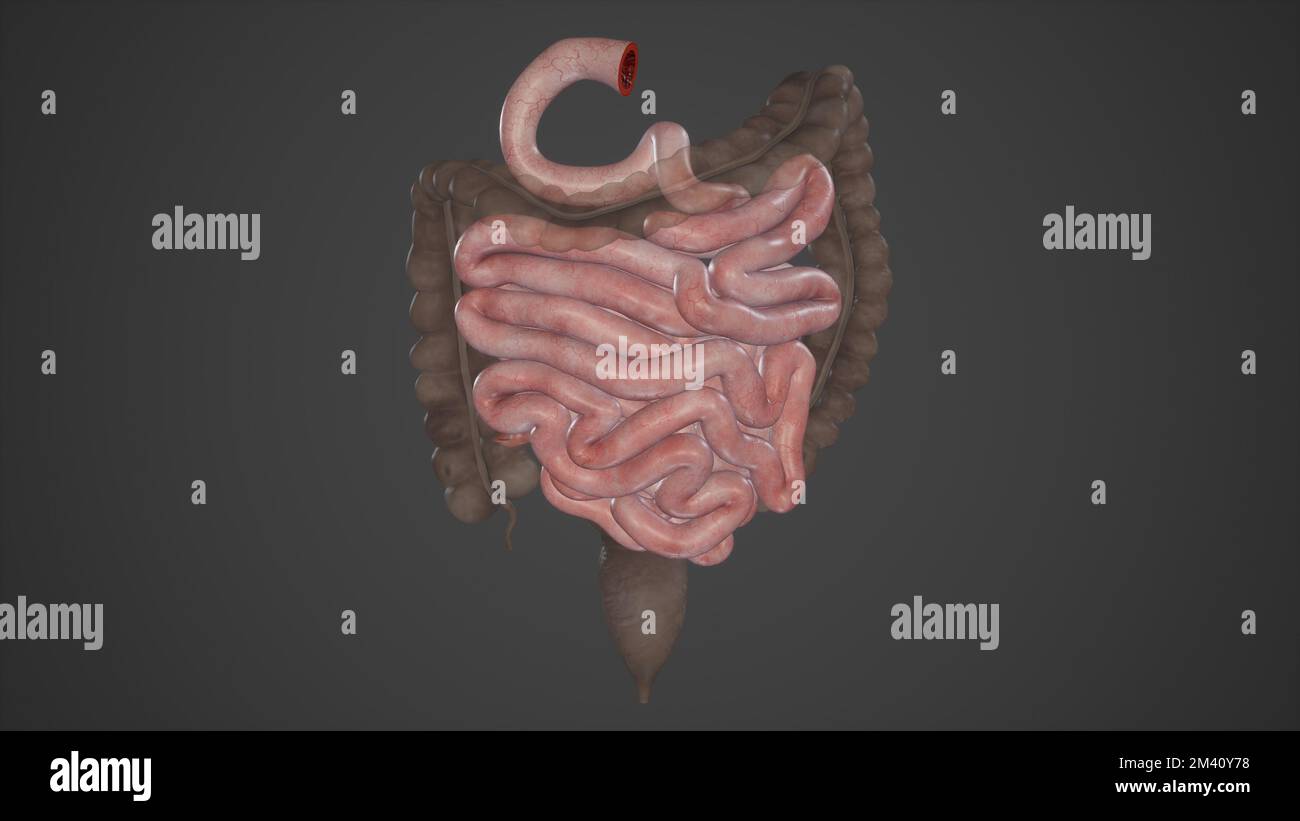

RFEWA8T8–Cavallo di piccole dimensioni trasversali del Colon - Cavallo Equus anatomia - isolato su bianco